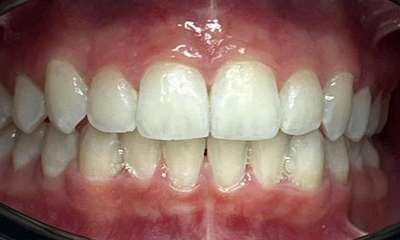

This patient was worried about the incisal edges of her front teeth that had become thin and prone to chipping. This had started in her twenties and unfortunately, now in her thirties, was progressing due to her deep and tight bite and minor crowding.

In her case, Dr Gourlay used 14 series of Invisalign aligners over 14 weeks to align her teeth into a more protected bite pattern. She then used composite bonding to restore the chipped edges. The patient has since moved on to using retainers at night to maintain and protect the position of the teeth.